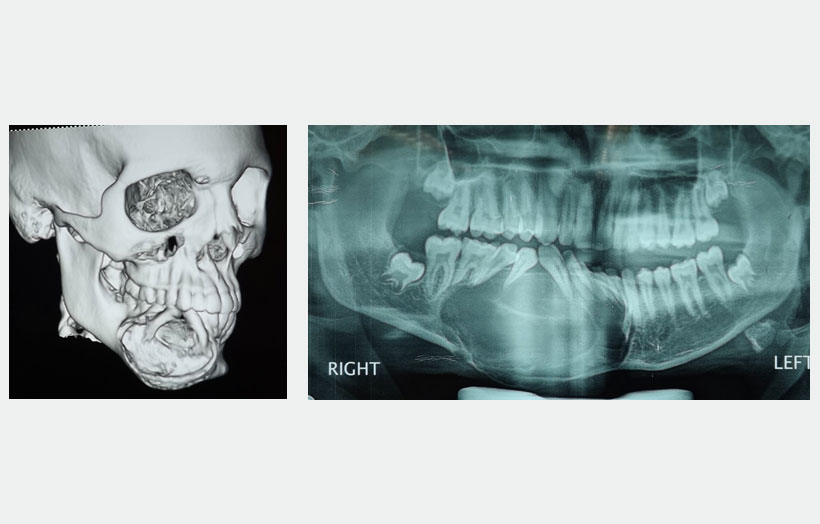

18 year old male patient came with chief complain of Swelling over Rt side of lower jaw. He was diagnosed as Benign Ossifying fibroma. Surgery was made in Feb 2013 for excision of lesion and reconstruction using Iliac crest cortico-cancellous bone graft from right side. Bone graft fixed to the defect using a reconstruction plate. After 1 year we can see adequate bone formation at the defect side. He is planed for replacement of missing teeth using 3 Alpha Dent 5×13 mm classic implants.